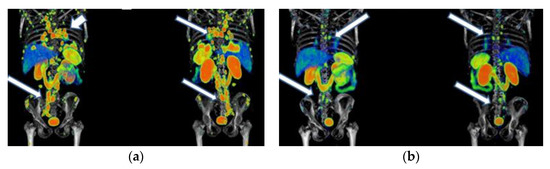

Figure 6. A 65-year-old woman was diagnosed with a well-differentiated neuroendocrine tumor of the intestine with metastases to the liver, mesenteric nodes, and abdominal implants. Due to disease progression, she was considered a candidate for therapy with 177Lu-DOTATOC (four doses of 7.4 GBq) in combination with octreotide. Response: partial response. She did not show any hematologic side effects. The last renal scintigraphy showed a slight decrease in renal tubular function with no changes compared to previous scintigraphy. (a) 68Ga-DOTATOC PET/CT imaging before 177Lu-DOTATOC therapy, (b) 177Lu-DOTATOC SPECT imaging (first dose), (c) 68Ga-DOTATOC PET/CT imaging one year after the first 177Lu-DOTATOC therapy.

Figure 7. A 48-year-old woman was diagnosed with a metastatic neuroendocrine tumor of the ileum. She received 177Lu-DOTATOC (four doses of 7.4 GBq) in combination with octreotide. Response: stable disease. No hematologic or renal toxicity. (a) 68Ga-DOTATOC PET/CT imaging before 177Lu-DOTATOC therapy, (b) 177Lu-DOTATOC SPECT imaging (first dose), (c) 68Ga-DOTATOC PET/CT imaging one year after the first dose of 177Lu-DOTATOC.

Figure 6, Figure 7 and Figure 8 show typical clinical cases of partial response and stable disease after 177Lu-DOTATOC therapy (the stable disease does not meet the criteria for partial response or progressive disease).